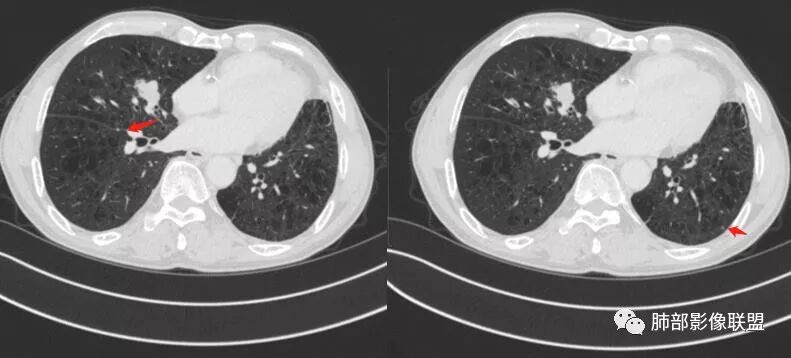

患者老年男性,间断咳嗽、咳痰伴痰中带血2个半月就诊,胸CT:右肺中叶内侧段占位性病变,病变可见分叶,周围可见结节影。病灶内可见厚壁空洞,洞壁光滑,未见洞壁结节,右肺中叶内侧段近肺门处支气管壁增厚。诊断:考虑结核,鉴别:肺癌,建议痰找抗酸杆菌、支气管镜检查

老年人,右肺中叶內侧段结节病灶,内见不规则空洞,近端可见引流支气管,其支气管壁增厚。结节病灶周围可见卫星灶,考虑肉芽肿病变,结核可能。

老年男性,肺气肿背景,右肺中叶结节,边缘膨隆,有分叶及细毛刺,厚壁空洞,考虑恶性,腺癌。

老年男性,咳嗽痰血,影像:肺气肿背景,右肺中叶结节,分叶膨隆为主,部分平直,空洞,内壁光滑,壁厚,未见索条?树芽征、引流支气管,考虑恶性,男性、肺气肿、小病灶空洞鳞癌可能性大,需要与TB鉴别。

右肺中叶内侧段实性病灶,病变可见深分叶,棘突,毛刺,周围多发结节影。病灶内可见厚壁空洞,内壁光滑,未见壁结节,增强轻度强化,右中叶内侧段支气管壁增厚。诊断:肉芽肿性病变,结核?隐球?鉴别:肺癌

晨读病例:患者老年男性,间断咳嗽、咳痰伴痰中带血2月余。实验室检查无明显异常升高。胸部CT:肺气肿背景,右肺中叶内侧段占位,密度不均,见分叶,边缘膨隆,部分可见边缘平直,支气管部分变窄、部分扩张,增强轻度强化,内可见低密度灶。综合考虑良性病变可能大,结核首先考虑,鳞癌待排。

老年男性,肺气肿背景,间断咳嗽、咳痰伴痰中带血2个半月,右肺中叶结节,边缘部分膨隆,部分平直,有小结节堆积感,中间空洞不规则,近端引流支气管扩张,壁增厚,这样的改变有三个可能,腺癌,鳞癌,结核,但小于3cm的腺癌一般不形成坏死空洞,更不会与支气管相通出现咳痰咳血症状,鳞癌小于3cm未经治疗也一般不与支气管相通,除非囊腔型鳞癌,但这个周围不是硬壳样改变。所以考虑结核可能。

晨读病例:老年男性,咳嗽痰中带血俩月,肺气肿背景,右肺中叶不规则结节影,有分叶,内有空洞还是扩张支气管?不均匀轻度强化,内有血管进入。考虑恶性肿瘤,鳞癌?

晨读:患者男性,68岁,间断咳嗽,咳痰伴痰中带血2个月。CEA轻度升高。肺气肿背景。左侧胸廓塌陷欠对称,右肺中叶结节,边缘膨隆有浅分叶,支气管未见明确鼠尾样截断,结节內似有点状偏高密度影,结节内是小空洞?还是扩张的支气管?结节周围未见卫星灶。叶间裂无牵拉,收缩不明显。腺癌放后吧,在鳞癌和结核之间鉴别,肯定建议支气管镜检查。考虑恶性,猜个鳞癌。

良恶性征象都有,恶性征象多于良性,空洞呈偏心,壁厚薄不均,首选恶性,TB放后。

老年男性,咳嗽痰血,肺气肿,右肺中叶结节,分叶膨隆为主,部分平直,空洞,内壁光滑,壁厚,轻度强化,考虑恶性,鳞癌?与TB鉴别。

LCNEC最常见的影像特征包括:(1)肿块发生部位:周围型肺癌为主,少数发生于肺中央。(2)肿块大小及形态。因肿瘤细胞生长迅速常形成较大肿块,因此其体积一般较大,直径常在3~10cm范围内,病灶常为不规则形软组织肿块。(3)肿块边界。多数学者报道大多数肿块边界清晰,边缘呈分叶状,毛刺征及“胸膜凹陷征”少见,认为与该病对周围组织浸润较轻及较少产生纤维瘢痕组织牵拉有关联。(4)肿块密度、强化特点及代谢情况。据文献报道,该类肿瘤因体积较大CT上常见软组织肿块,且多数密度不均匀,内见囊变坏死区,增强后呈轻或中度不均匀强化(可见强化者占75.7%),认为其强化特点与其内部肉眼可见坏死灶和肿瘤较大直径有关。(5)伴随症状及远处转移。该病恶性程度高,侵袭性强,常侵犯邻近结构,如胸膜、心包、邻近骨质或纵隔内组织等,易出现纵隔淋巴结转移,部分发生肺内及远处转移,少数早期可出现广泛远处转移。

LCNEC患者空洞、钙化、阻塞性肺炎、肺不张、积液这些CT特征较少见,少见支气管充气征。